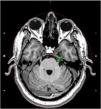

Materials and methodsFifty-three patients with typical TGN underwent GKRS from May 2012 until December 2022. Among these patients, 45 patients who were follow-up for at least 12 months were included in the study. A mean dose of 87.5 Gy (range, 80–90) was administered to the trigeminal nerve. Postoperatively, outcome was considered excellent if the patient was pain- and medication-free.